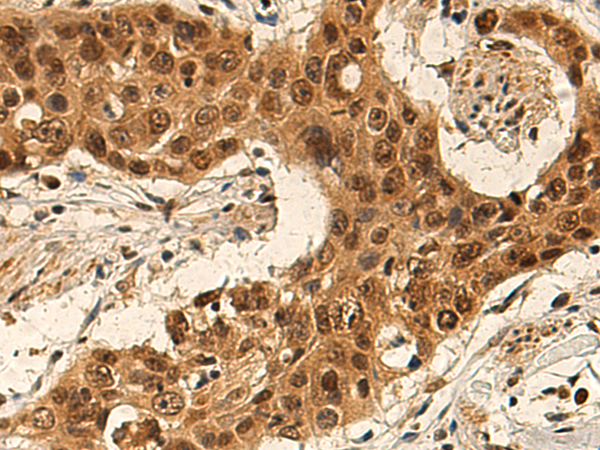

分类: 科研抗体货号: P01664别名: G4-1; G5pr; C14orf10应用: IHC反应种属: Human, Mouse, Rat